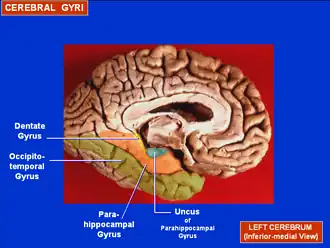

Human brain inferior-medial view. Parahippocampal gyrus labelled as #5